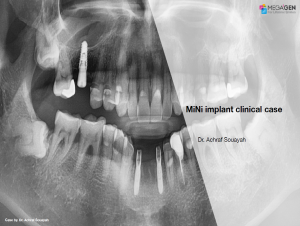

Miguel Stanley, Filipa Calheiros Braga, and Beatriz Mota Jordao, AnyRidge, Immediate Loading, Anterior Maxilla, Scientific background, single replacement